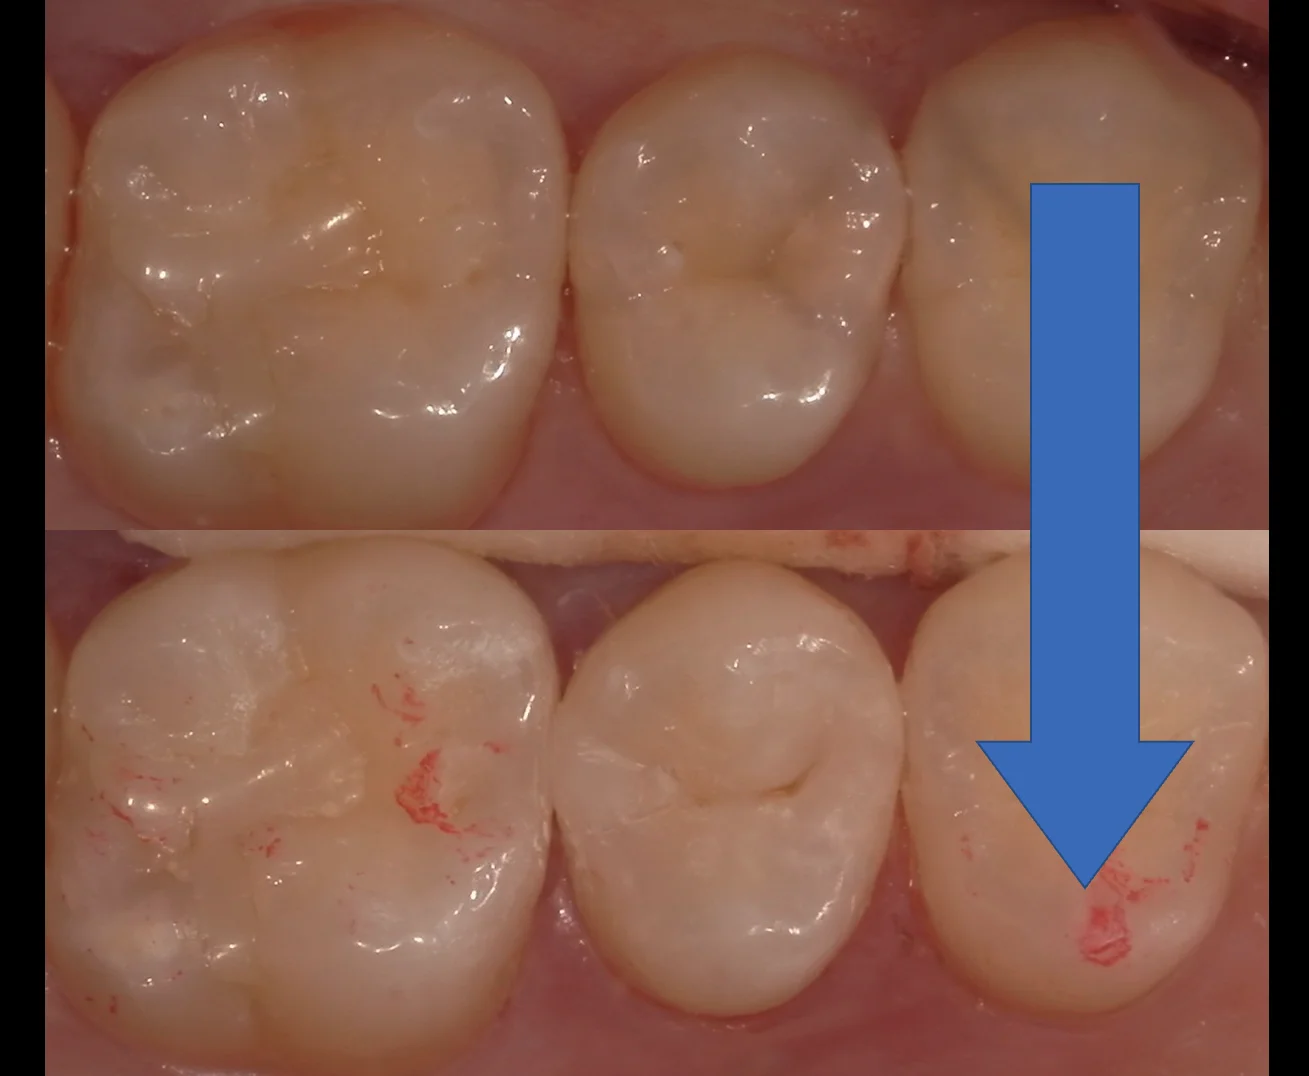

1人目はこちらの、他の医院にて勤務されている歯科衛生士の方です。

処置当日がこちらです。リンク先からも確認できますが、術前の写真がピンボケしているという大ポカをしでかしてしまいましたので、虫歯を取り切った状態の写真からのスタートです。

噛む面のみならず、上下の噛み合わせがしっかりと当たる場所も歯がなくなってしまっています。

1年後の経過の写真がこちらになります。

黒いまるで囲ったところの変化を見て欲しいのですが、やや削れてるのがわかるかと思います。

とはいえ、1年経ってこの程度の変化なんですね。

噛み合わせは年々変化して行きますし、それに伴って同様な感じですり減ってくれるため、ダイレクトボンディングは実は長期的な安定をしやすいものだと個人的には思っています。